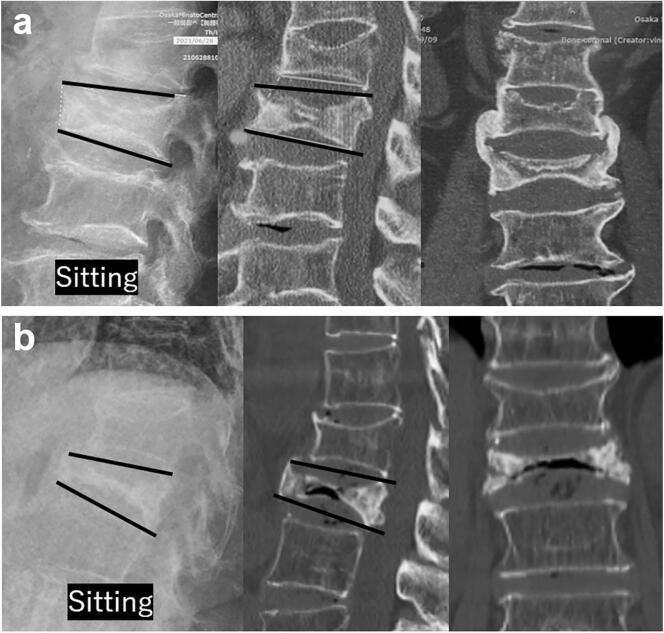

This was post hoc analysis of a prospective, multicenter, observational study conducted across 8 hospitals, enrolling 144 patients with conservatively treated OVF, grouped into patients receiving bisphosphonate (BP,  = 55), teriparatide (TPTD,  = 62), and romosozumab (Romo,  = 27). The primary outcome was the incidence of subsequent OVF at 3 and 12 months, whereas the secondary outcomes included the incidence of pseudoarthrosis and progression of vertebral collapse (VC). Pseudoarthrosis was classified as stable or unstable based on vertebral instability.

The use of osteoanabolic agents did not reduce the incidence of subsequent OVF at 3 and 12 months. There were no significant differences in the background data or type of conservative treatment among the three groups. However, the TPTD and Romo groups had significantly lower rates of unstable pseudarthrosis ( = 0.03). Additionally, there were no significant differences in VC progression between groups, but it tended to be higher in the BP group than the TPTD and Romo group ( = 0.07).